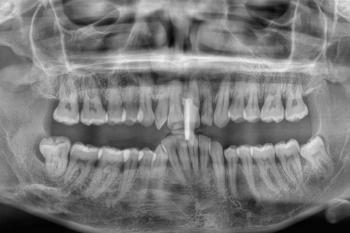

Full dental X-ray or CBCT scan

This X-ray shows a severe dental abscess with jawbone involvement, a critical condition requiring urgent professional treatment. Early intervention can stop the infection and preserve remaining bone structure.